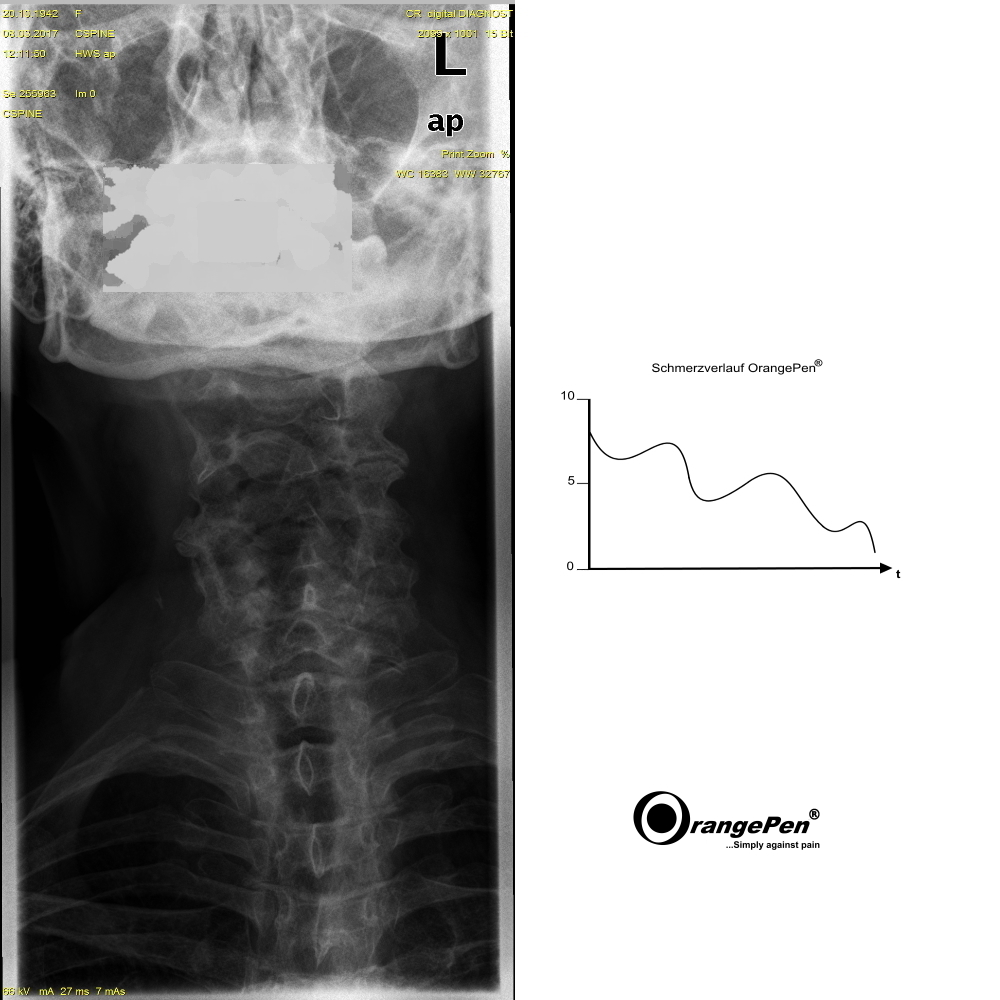

Sore throat and neck pain

Sore throat and neck pain treated with OrangePen®

The pain was reduced to a tolerable level. Patient presents herself when the pain deteriorates again.